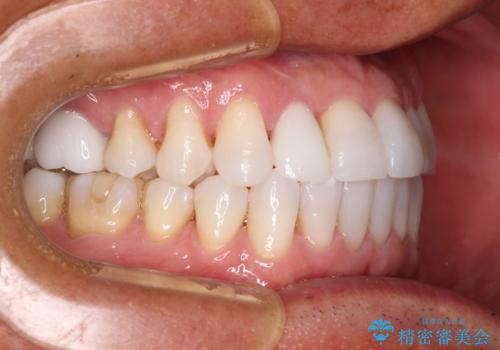

治療途中の前歯を治したい インビザライン矯正とオールセラミッククラウン

- 治療途中の前歯と上下前歯のデコボコ気にして来院された患者様です。

前歯のデコボコはインビザラインにより歯列を整え、その後に、前歯などをオーダーメイドタイプのオールセラミッククラウンにて補綴治療することとしました。

長時間のマウスピース装着に協力いただき、短期間で歯列をしっかりと改善することができました。

ホームホワイトニングを併用していただいたので、とても明るい口元に仕上がり、患者様には大変満足していただきました。